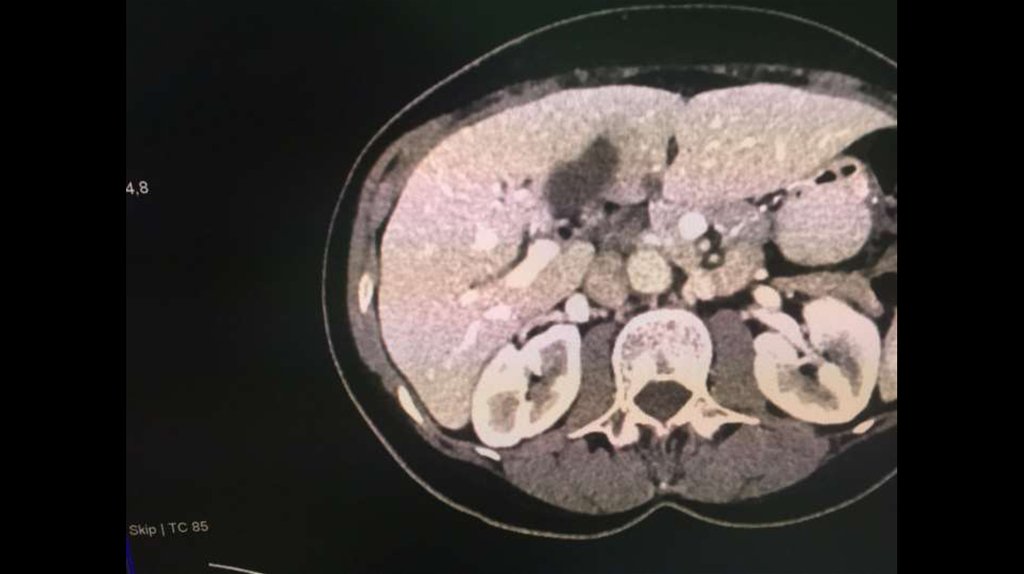

По направлению из ЦГБ в ККБ №1 поступил пациент М., 48 лет, с диагнозом «Эхинококкоз

печени»

Пациенту в плановом порядке выполнено КТ ОБП. По результатам исследования выявлена

эхинококковая киста IV-V сегментов.